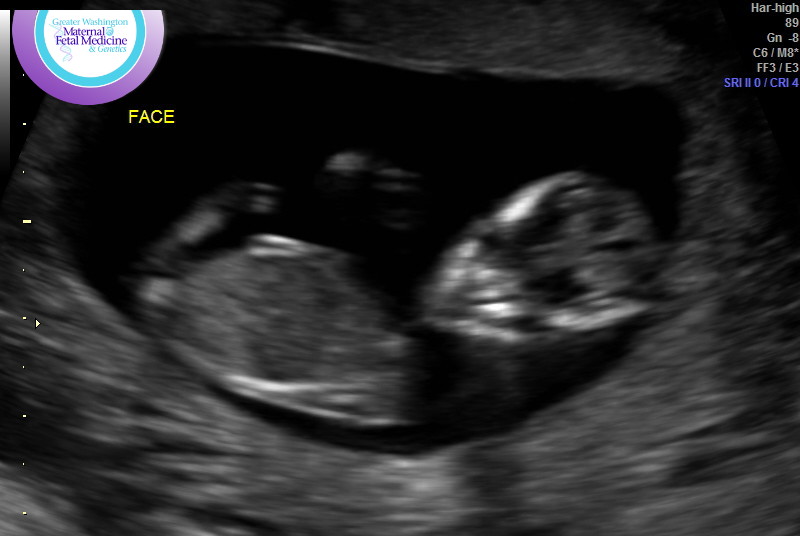

Here are the nub/skull pics again:

Attachment 41115Attachment 41116Attachment 41117Attachment 41118Attachment 41119